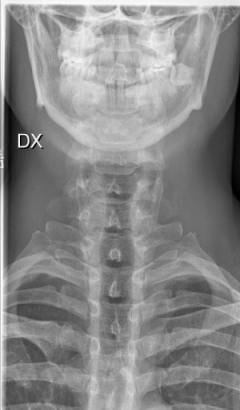

Ofta har whiplashskador ingen synlig påverkan på strukturerna i nacken enligt röntgenläkarens utlåtande. Smärta och problem kan uppstå ändå. Om våldet är stort kan självklart skador synas i röntgenundersökningar. Detta är dock inget som måste föreligga för att diagnosen whiplash ges.

Röntgen nacke

Vid allvarligare olycka med inblandat nackvåld, gör man en slätröntgen (”vanlig röntgen”) för att se om det uppstått skada på skelettet. Man kan även göra en MR då man ser skador på mjukdelarna, detta är vanligast om pasienten har allvarligare neurologiska besvär eller det är en långvarig problematik man vill utreda. I de flesta fall har en pisksnärtskada inga fynd från undersökningarna från slätröntgen eller magnetisk resonanstomografi.